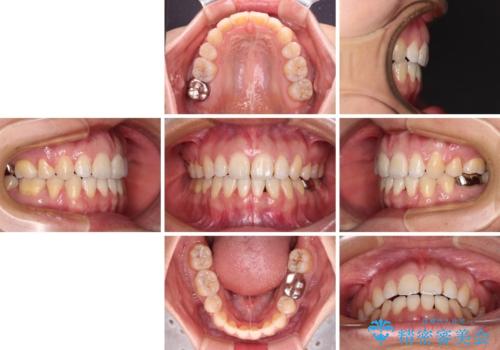

- 治療期間

- 2年

骨格的に下顎がやや前方にあるため、横顔のシルエットが著しく変化することはありませんでしたが、口元はスッキリと引っ込み、唇が閉じやすくなりました。